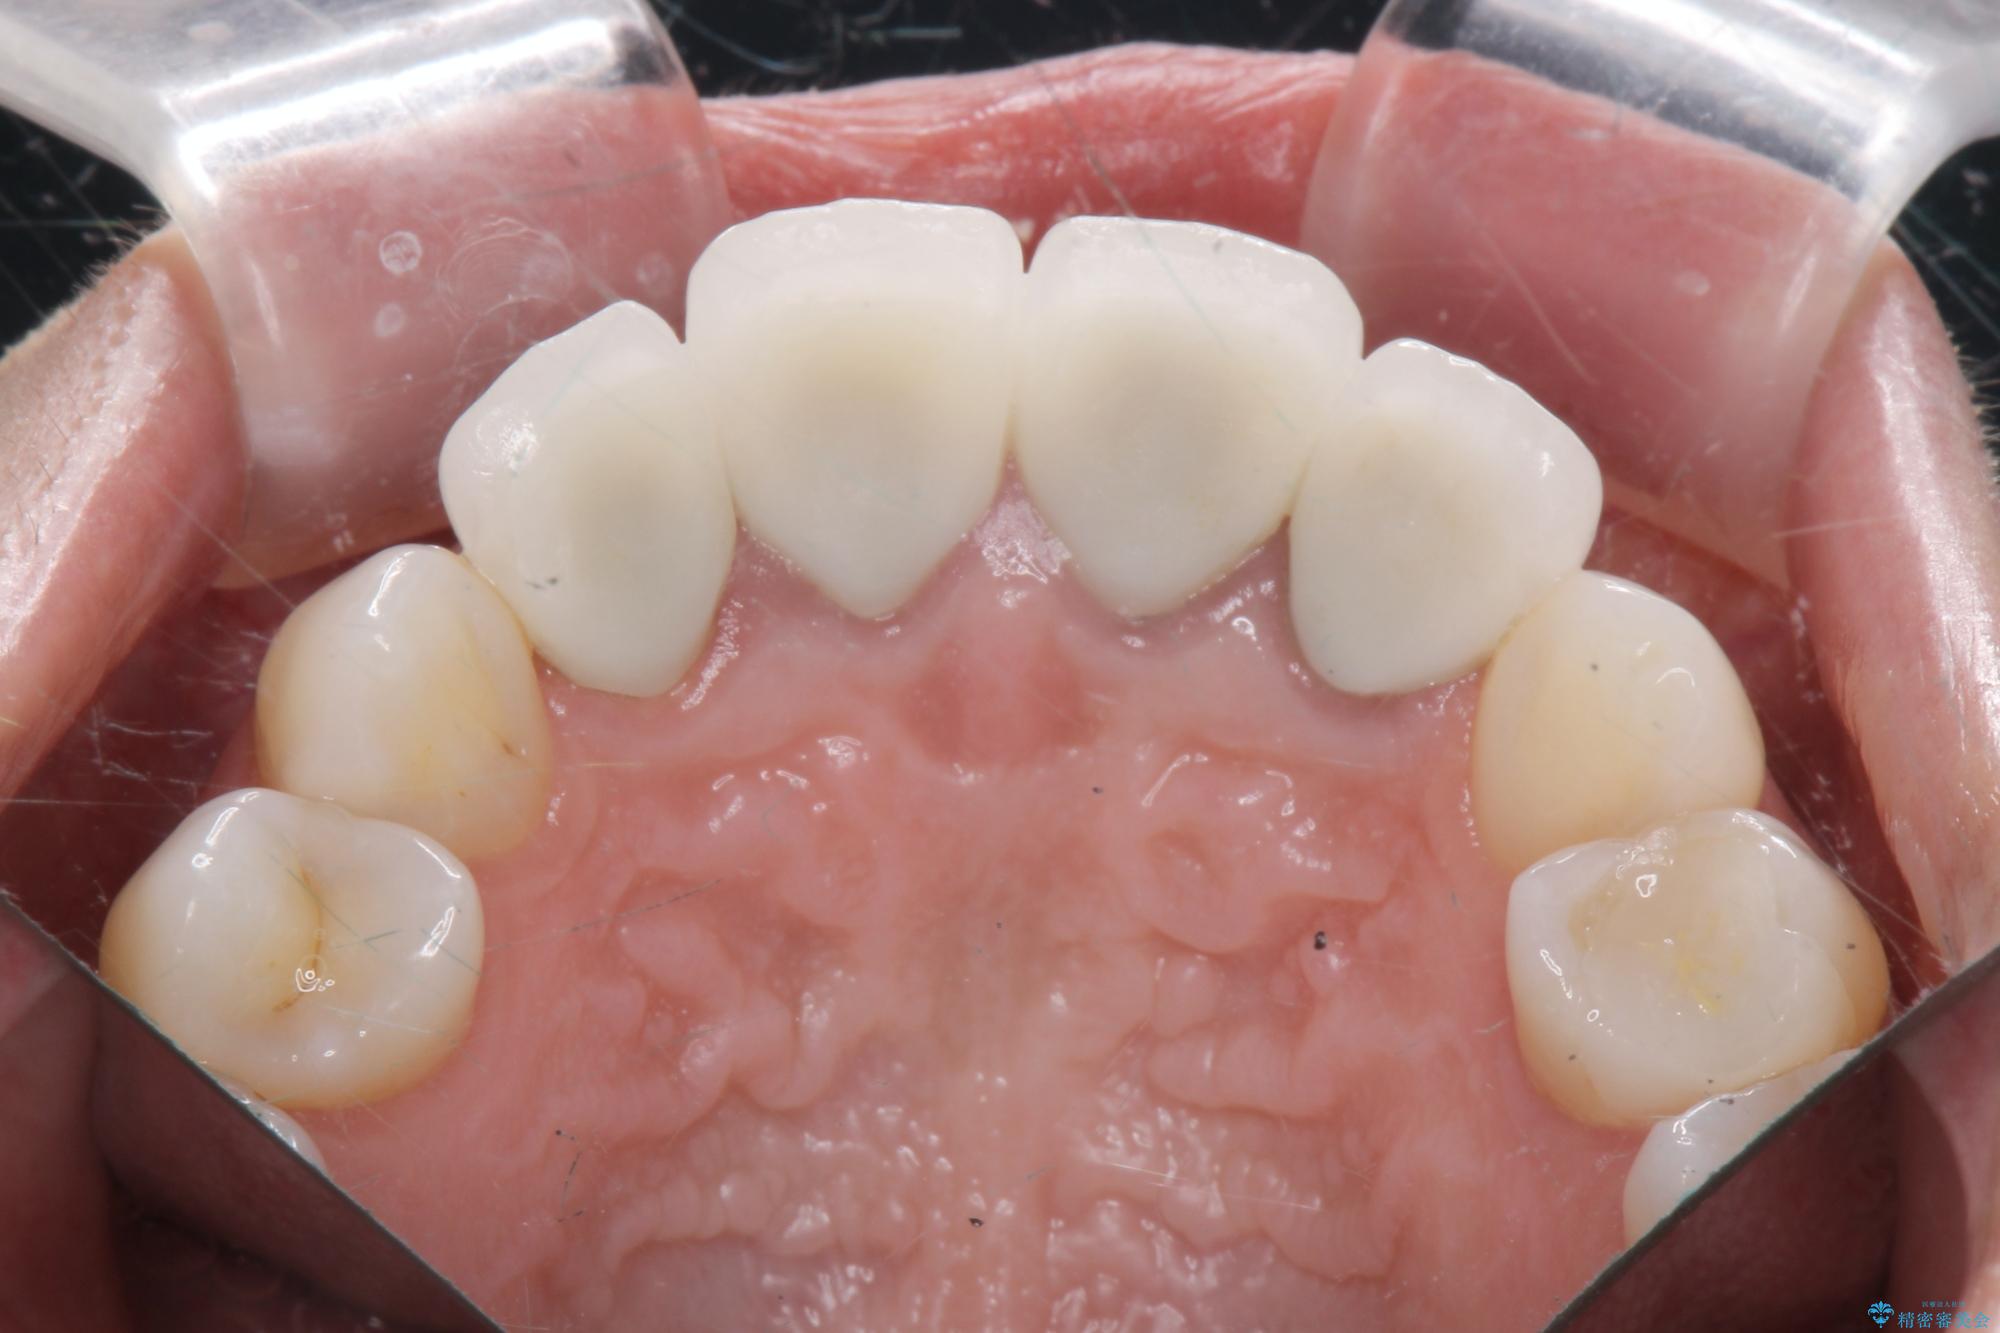

• 概算治療費:66万円(ジルコニアクラウン×5・仮歯×5)※費用は治療当時の料金となります

治療を終えて

歯槽堤保存術を併用したブリッジ治療 治療後画像 歯槽堤保存術を併用したブリッジ治療 治療後画像 歯槽堤保存術を併用したブリッジ治療 治療後画像 歯槽堤保存術を併用したブリッジ治療 治療後画像 歯槽堤保存術を併用したブリッジ治療 治療後画像 歯槽堤保存術を併用したブリッジ治療 治療後画像 歯槽堤保存術を併用したブリッジ治療 治療後画像